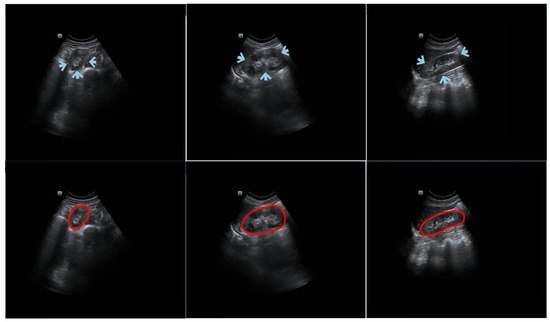

3.1. Comparison with Different Variants

Table 2 represents the testing outcomes of four variant models based on the DSC value. Figure 5 represents the visual qualitative results of the four variant models based on two randomly selected cases. Parallel architectures (Parallel 1 and 2) showed better performance than serial architectures (Serial 1 and 2), with DSC and Ω values of 0.89 and 0.899 and 0.805 and 0.813, respectively, for the two parallel architectures. However, compared with Parallel 1, the DSC and Ω values of Parallel 2 increased by 1.01% and 0.99%, respectively. Hence, we used Parallel 2 as the coarse segmentation step of our proposed method.

As shown in Table 2, different serial and parallel architectures resulted in different levels of performance for the coarse segmentation strategy. There are three aspects of the outcomes presented in Table 2 to be discussed. First, overall, the parallel architecture showed better capability than the serial architecture. Both the AG [18] and SE [19] modules are known to have a good ability to boost relevant features and remove irrelevant features. However, using serial AG and SE modules may cause the deletion of a large amount of information, some of which may be useful. Second, of the serial architectures evaluated, SE-AG (Figure 3b) showed better performance than AG-SE (Figure 3a). The main reason for this is that the AG module has a more complex structure than the SE module (as shown in Section 2.3), which makes it difficult to train the AG module and avoid the loss of meaningful information. Third, as illustrated in Table 2, the Parallel 2 model performed better than the Parallel 1 model. The main difference between these two parallel architectures is in the input for the SE module, with one using features from the decoding path (Parallel 1) and the other using features from the encoding path (Parallel 2). Parallel 2 may perform better because using encoding features as the input for the SE module carries the merit of the SE module to emphasize meaningful features and suppress less useful features.

Figure 5. Visual results of four variant models. Two randomly selected cases are presented under different views. The blue and red lines show the experimental outcome and GT, respectively. The first two rows show the axial view, and the last two rows show the sagittal view. The first and third rows show the overlap between the segmentation result and the GT. The second and fourth rows show the corresponding zoomed-in display.